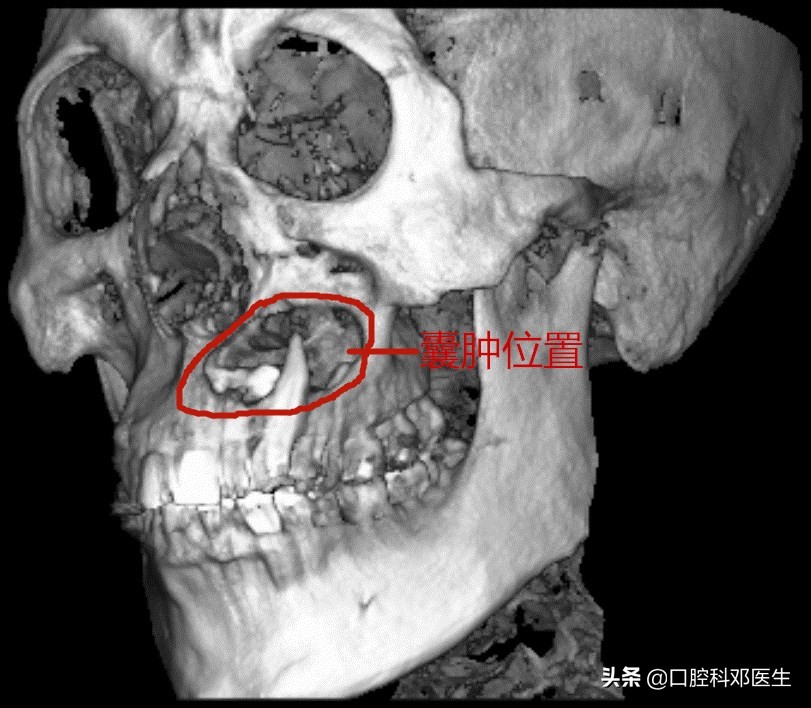

40岁严某最近20天比较苦恼,朋友们都说他脸肿了,平时也不痛不痒的,怎么脸就像吹气球样的越来越肿了呢?而且连张口都困难了。于是他来到长沙市中心医院口腔科检查,一检查牙齿和口腔都没有问题,医生建议他拍个口腔X线片看看,不照不知道,一照吓一跳,X线片显示他的左侧上颌骨已经被吃空了,必须住院进行上颌骨囊肿根治手术。

接诊的邓医生介绍:这位患者脸肿大是由于左侧上颌骨内一个埋伏多生的牙齿所引起的,由于牙齿无法正常萌出,经过时间的积累,从而诱发囊肿,囊肿一般都不痛不痒,越长越大,像鼓气球一样,逐渐破坏了周围的骨头,如破坏上颌骨前壁,就会突破至软组织,引起脸部肿大;如破坏牙槽骨,则会导致牙齿松动移位,引起牙根吸收疼痛等症状。